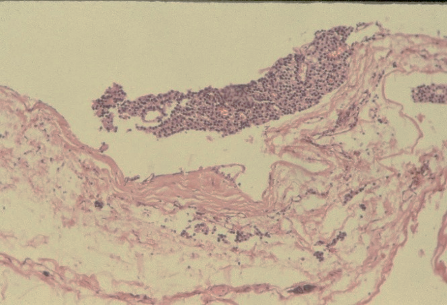

Ans to previous : (August 2025)

Tumour embolus in a lymphatic channel.